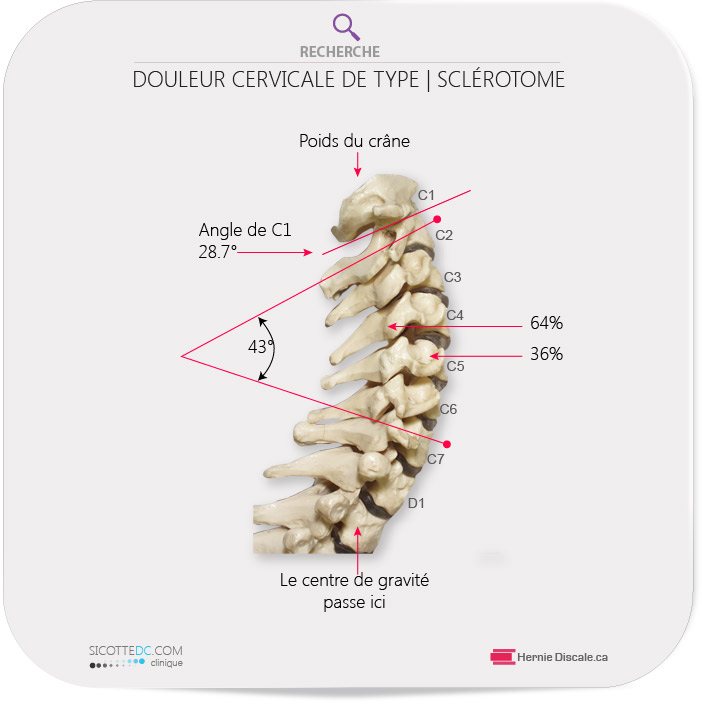

Les effets d’une courbure cervicale adéquate

Un cou normal répartit 64 % du poids du crâne au niveau des facettes articulaires (partie postérieure) comparativement à 36 % sur le corps vertébral (partie antérieure). La perte de la courbe cervicale transfère le poids du crâne sur la partie avant des vertèbres, et conséquemment, crée un stress sur la partie postérieure qui s’hypertrophie pour cause d’instabilité. Selon la loi de Wolff, ce transfert de poids crée des dépôts osseux additionnels. L’anatomie de la colonne cervicale nous indique qu’elle est construite pour recevoir les forces de compression vers l’arrière, et les forces de traction vers l’avant. Ceci ne peut se produire que lorsque le cou possède une courbe normale. Tout redressement du cou causerait du stress sur le corps vertébral antérieur. Harrison a démontré que ceci peut être la cause d’une dégénérescence prématurée du cou.